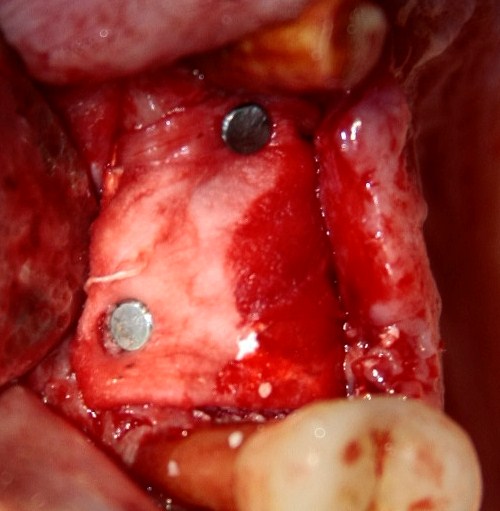

Что же касается нерезорбируемых мембран… Было дело, работал с Gore-Tex (дорого, очень дорого), титановыми сетками (заколебался потом доставать) и тефлоновыми Cytoplast:

результат:

или

с трудом выковыриваем сетку и ищем имплантат:

чтобы поставить формирователь: